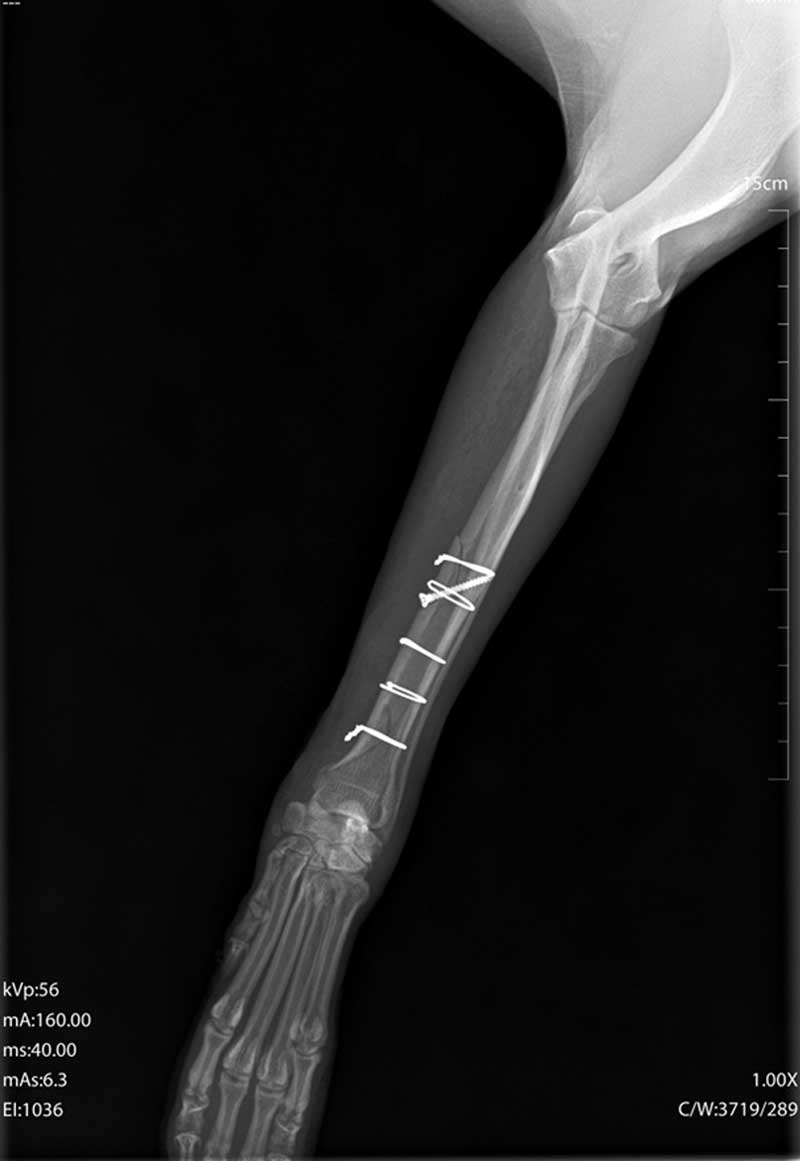

Dijagnoza se postavlja rendgenskim snimkama koje pokazuju lokaciju i tip prijeloma.

Liječenje može biti konzervativno, pomoću gipsa ili udlage, ili kirurško, uključujući pločice, vijke, čavle ili vanjsku fiksaciju.

Kirurško liječenje omogućuje precizno poravnanje kostiju i stabilnost tijekom cijeljenja, što skraćuje vrijeme oporavka.